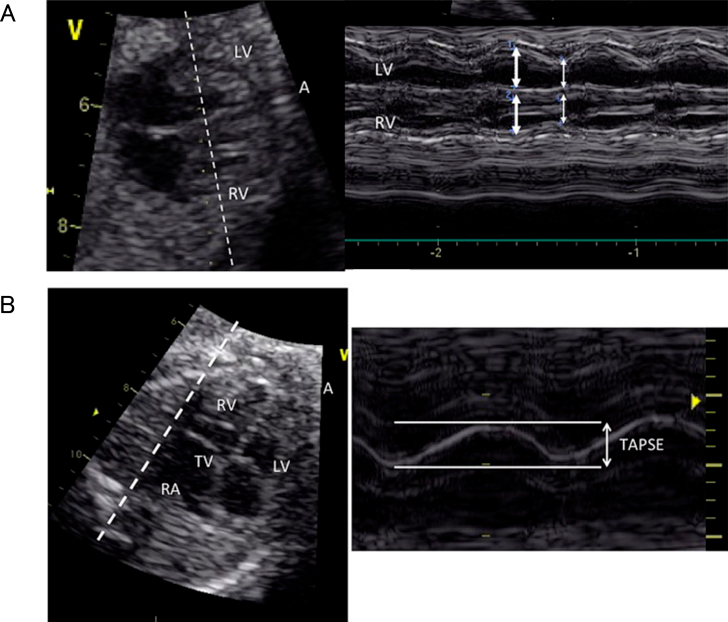

2. 心室収縮機能評価

心機能の評価として最も直接的と考えられるのが心室収縮機能の評価であるが,胎児では胎位によって常に一定の角度で心臓の断面を描出できるわけではないこと,胎児の心電図が通常の方法では得られないことから,心室収縮機能の評価に用いることのできる方法は出生後と比較して限定される.現在用いられるのは心室内径短縮率(Fractional Shortening; FS)/心室駆出率(Ejection Fraction; EF)とdP/dt,収縮期僧帽弁/三尖弁輪移動距離(Mitral/Tricuspid Annular Plane Systolic Excursion; MAPSE/TAPSE),心室の統合機能評価として後述するMyocardial Performance Index(MPI)があげられる1, 5)

2.2 MAPSE/TAPSE

左室・右室の長軸方向の収縮機能指標で,僧帽弁輪自由壁側/三尖弁輪自由壁側の長軸方向の移動距離がそれぞれMAPSE/TAPSEである.心尖が12時もしくは6時方向になるように四腔断面像を描出し,カーソルを心室中隔と平行になるように置いてM-mode法を用いて計測して算出される(Fig. 4B).これまでに複数の正常値(Z値)が報告されているほか,双胎間輸血症候群,胎児心不全,母体糖尿病などで検討されている8)

正常単胎の胎児ではMAPSEとTAPSEは在胎週数と共に大きくなり,MAPSEのほうがTAPSEより小さい.

なお,出生後の心エコーではTAPSEはセクタプローブを使用して心尖部四腔断面において三尖弁輪にカーソルを置いて計測するため,心室中隔には平行ではなく厳密には計測の方向が異なっている.

長軸方向の収縮機能指標としては組織ドプラ法によるS’(収縮期房室弁輪最大移動速度)を用いた評価についても報告されている.

Pediatric Cardiology and Cardiac Surgery 41(1): 11-19 (2025)

Fig. 4 Mモード心エコー法を用いた両心室のFractional Shortening(FS)の計測(A)と三尖弁輪収縮期移動距離(TAPSE)(B)の計測

文献21)より引用.

ただし,FSは立体的な構造をしている心室の一方向の機能しか評価できず,胎児では左室圧と右室圧が等圧で短軸像の心室中隔が扁平であること,右室は更に複雑な形態をしていることからより不正確と考えられることに注意が必要である.FSは現在の日本循環器学会の「循環器超音波検査の適応と判読ガイドライン」では左室収縮能の評価項目に記載されていない6)